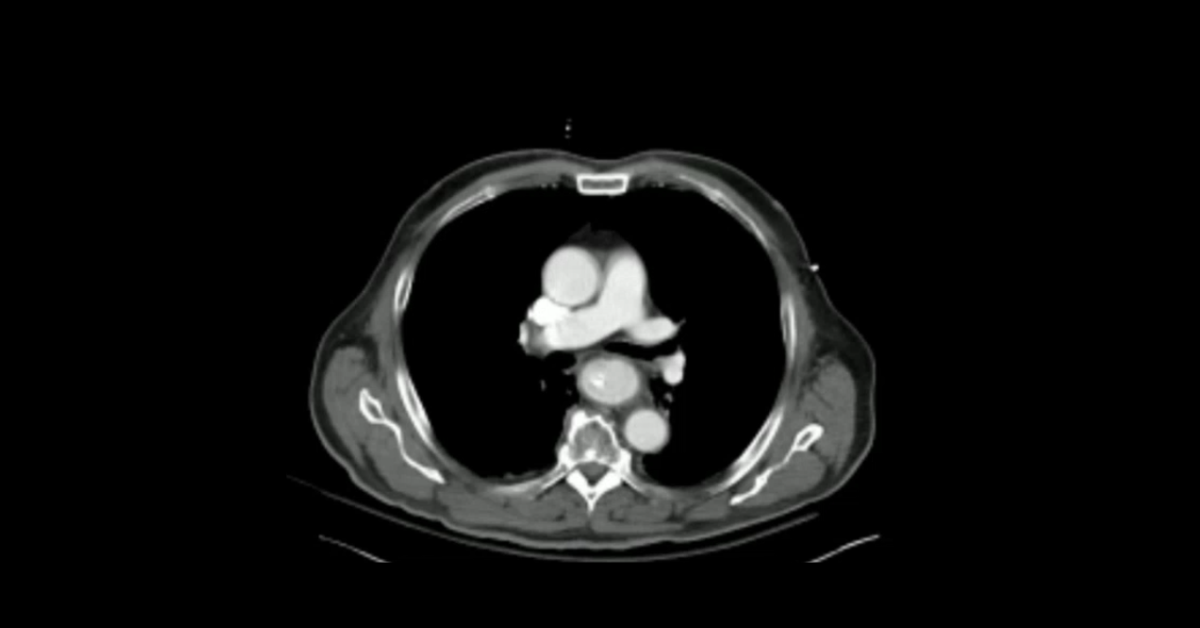

Presented by Ashish Khandelwal, MBBS, MD at Practical Radiology 2025. This talk will allow you to understand appropriate use of multimodal imaging in pregnant patient and know the imaging features of commonly encountered acute abdominopelvic conditions during pregnancy.